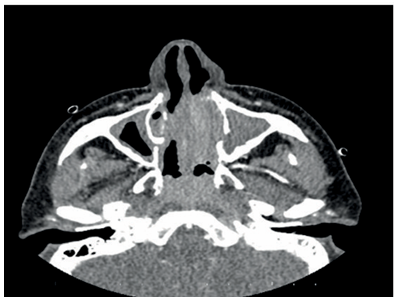

The patient, who has been under observation for approximately one year, presented to us with newly developed skin lesions due to the lack of regression in symptoms during follow-up. Lesions were observed on the distal tibia in front of the ankle, characterized by scattered, intense, pink-red petechial-style spots, and the formation of plaques by their combination (Figure 2). Mild coarse rales were present upon auscultation of the respiratory system. Other system examinations were normal. Blood pressure: 130/70, pulse: 105, respiratory rate: 20, saturation: 91. Total IgE was 3990, and peripheral blood eosinophils were 63% (1800). ANA, RF, and other collagen markers, as well as p-ANCA and c-ANCA, were negative. Parasitological examination of the stool yielded negative results. Echocardiography and abdominal ultrasound were evaluated as normal. Sinus CT revealed widespread mucosal thickening and opacifications related to secretion in the paranasal sinuses (Figure 3). A skin biopsy showed eosinophil-rich vasculitic changes, consistent with Churg-Strauss syndrome (CSS). The patient, diagnosed with CSS based on clinical, laboratory, and pathological findings, was started on cyclophosphamide treatment and is currently under our follow-up.

Figure 3. Widespread mucosal thickening and opacifications related to secretion in the paranasal sinuses